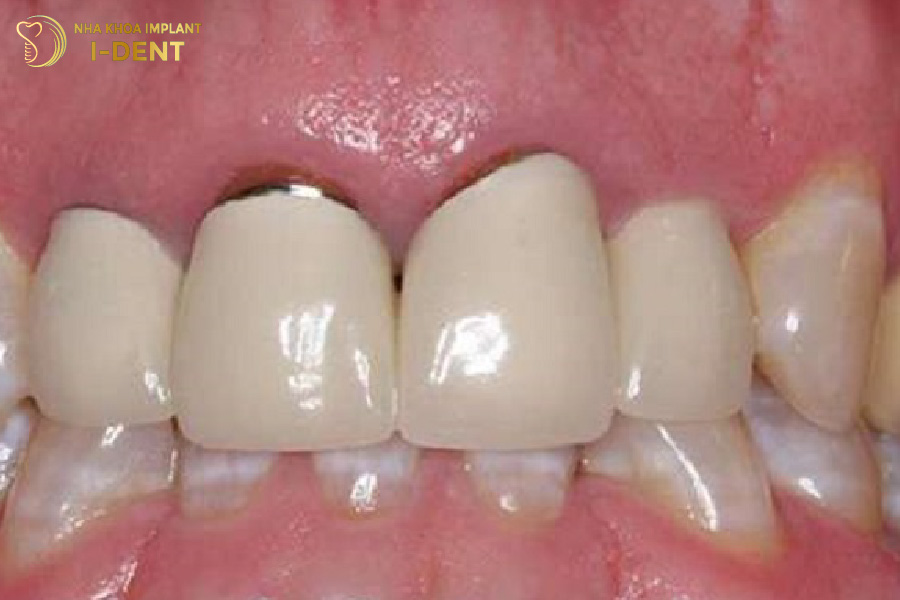

- Ảnh hưởng thẩm mỹ

Răng sứ bị hở chân sẽ làm lộ phần cùi răng bên trong, xuất hiện cả tình trạng đen viền nướu, khiến cho khuôn mặt mất thẩm mỹ. Nụ cười trở nên kém duyên, thiếu tự nhiên.

Hở chân răng sứ gây mất thẩm mỹ nụ cười